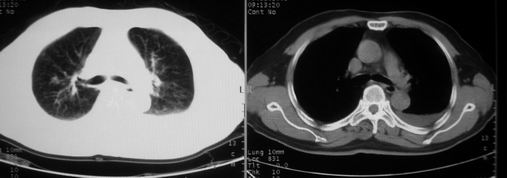

男,78岁,咳嗽、咳痰、发热入院,抗炎治疗一周后已退热,咳血似痰。

10月3日片: